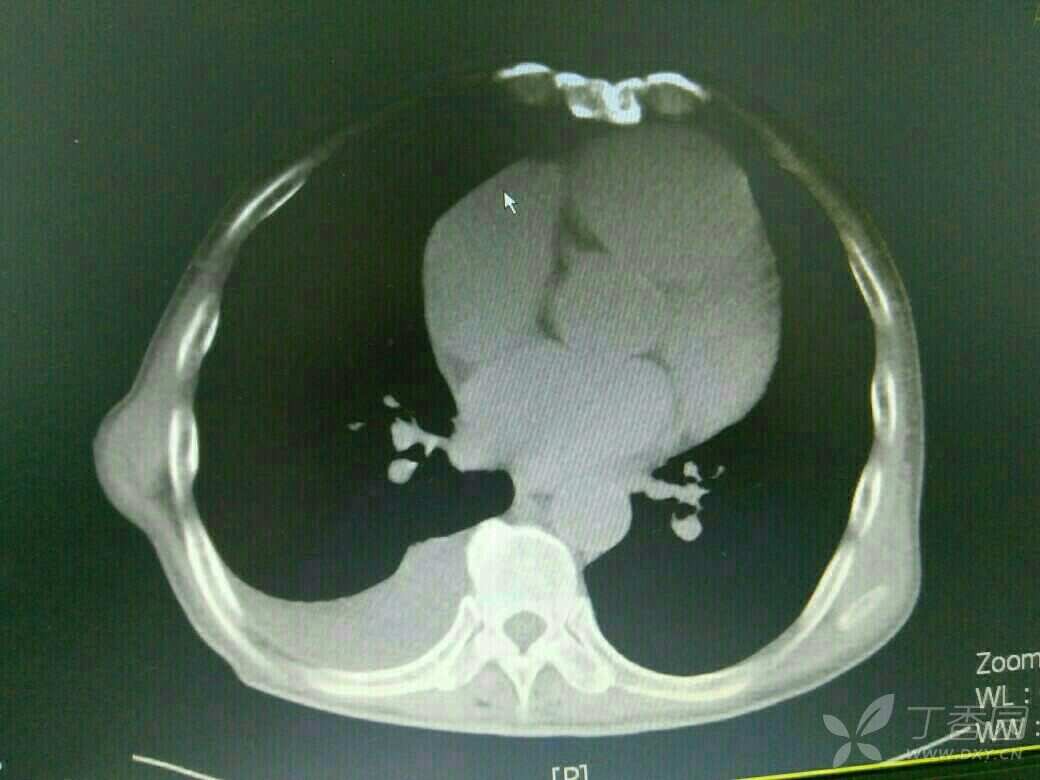

患者71岁老年男性,既往copd,多次住院治疗,平时状态好的时候气促也明显,这次是受凉在当地输液10多天,病情加重入院,来的时候诉乏力气促,上腹胀痛,不能进食,双下肢中度水肿,颈静脉怒张,肝功提示转氨酶400多,bnp6000多,心电图是快速房颤,心脏彩超示EF26%,CT示双侧胸腔积液,肝周积液,门静脉增宽,直径1.8cm,与强心利尿后,来的时候血气还可以,现在血气是呼酸合并代碱